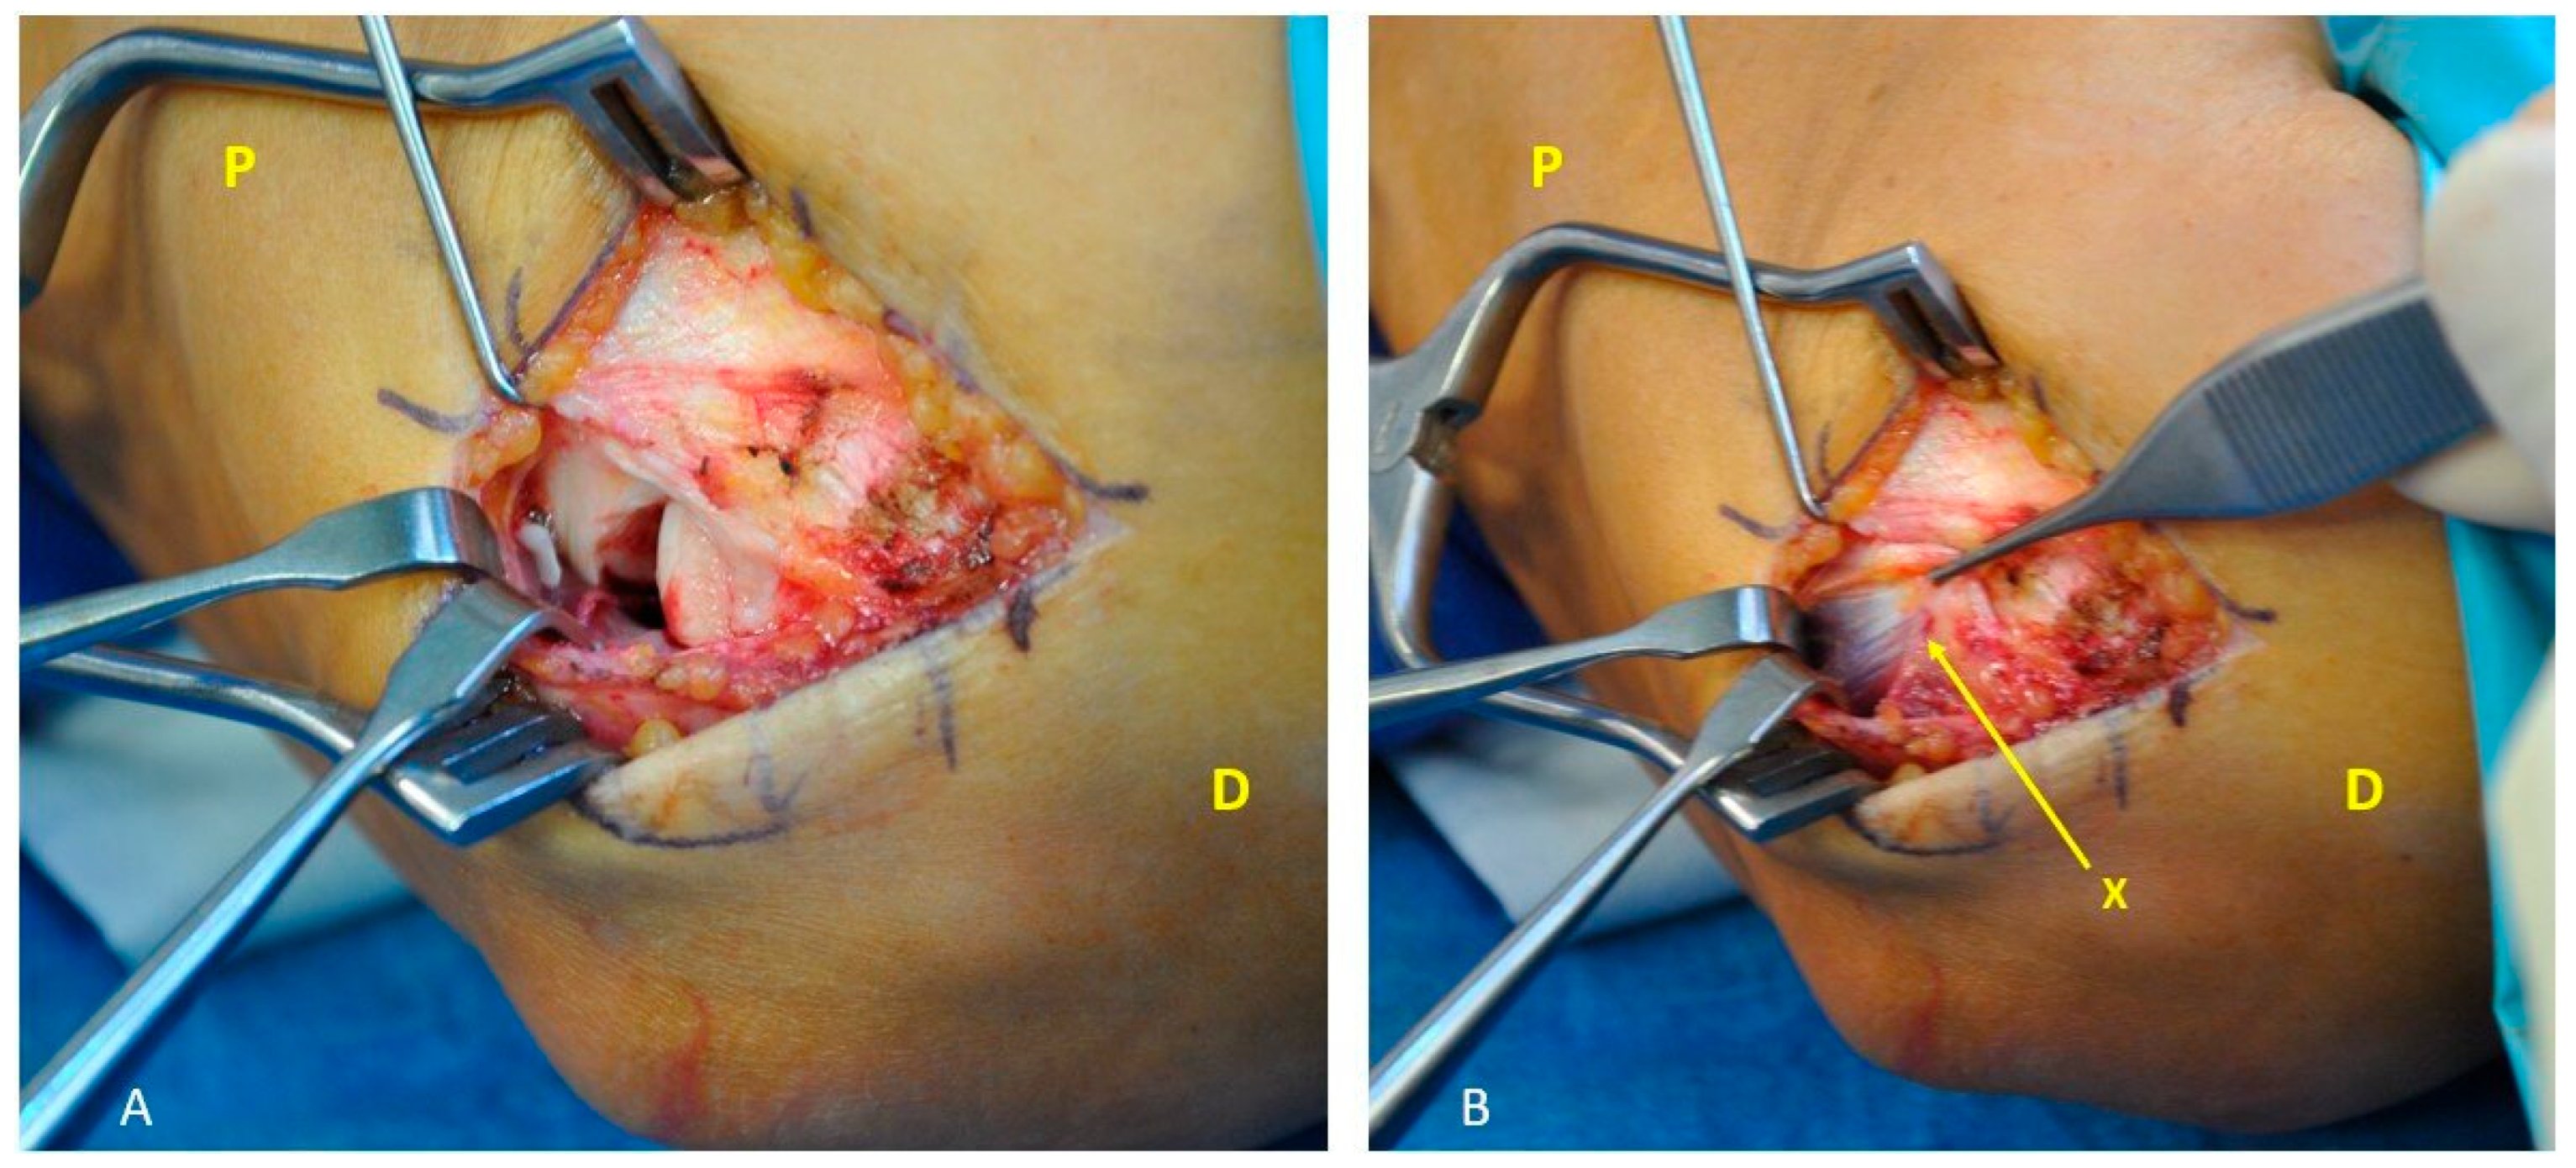

2.2. Surgical Technique